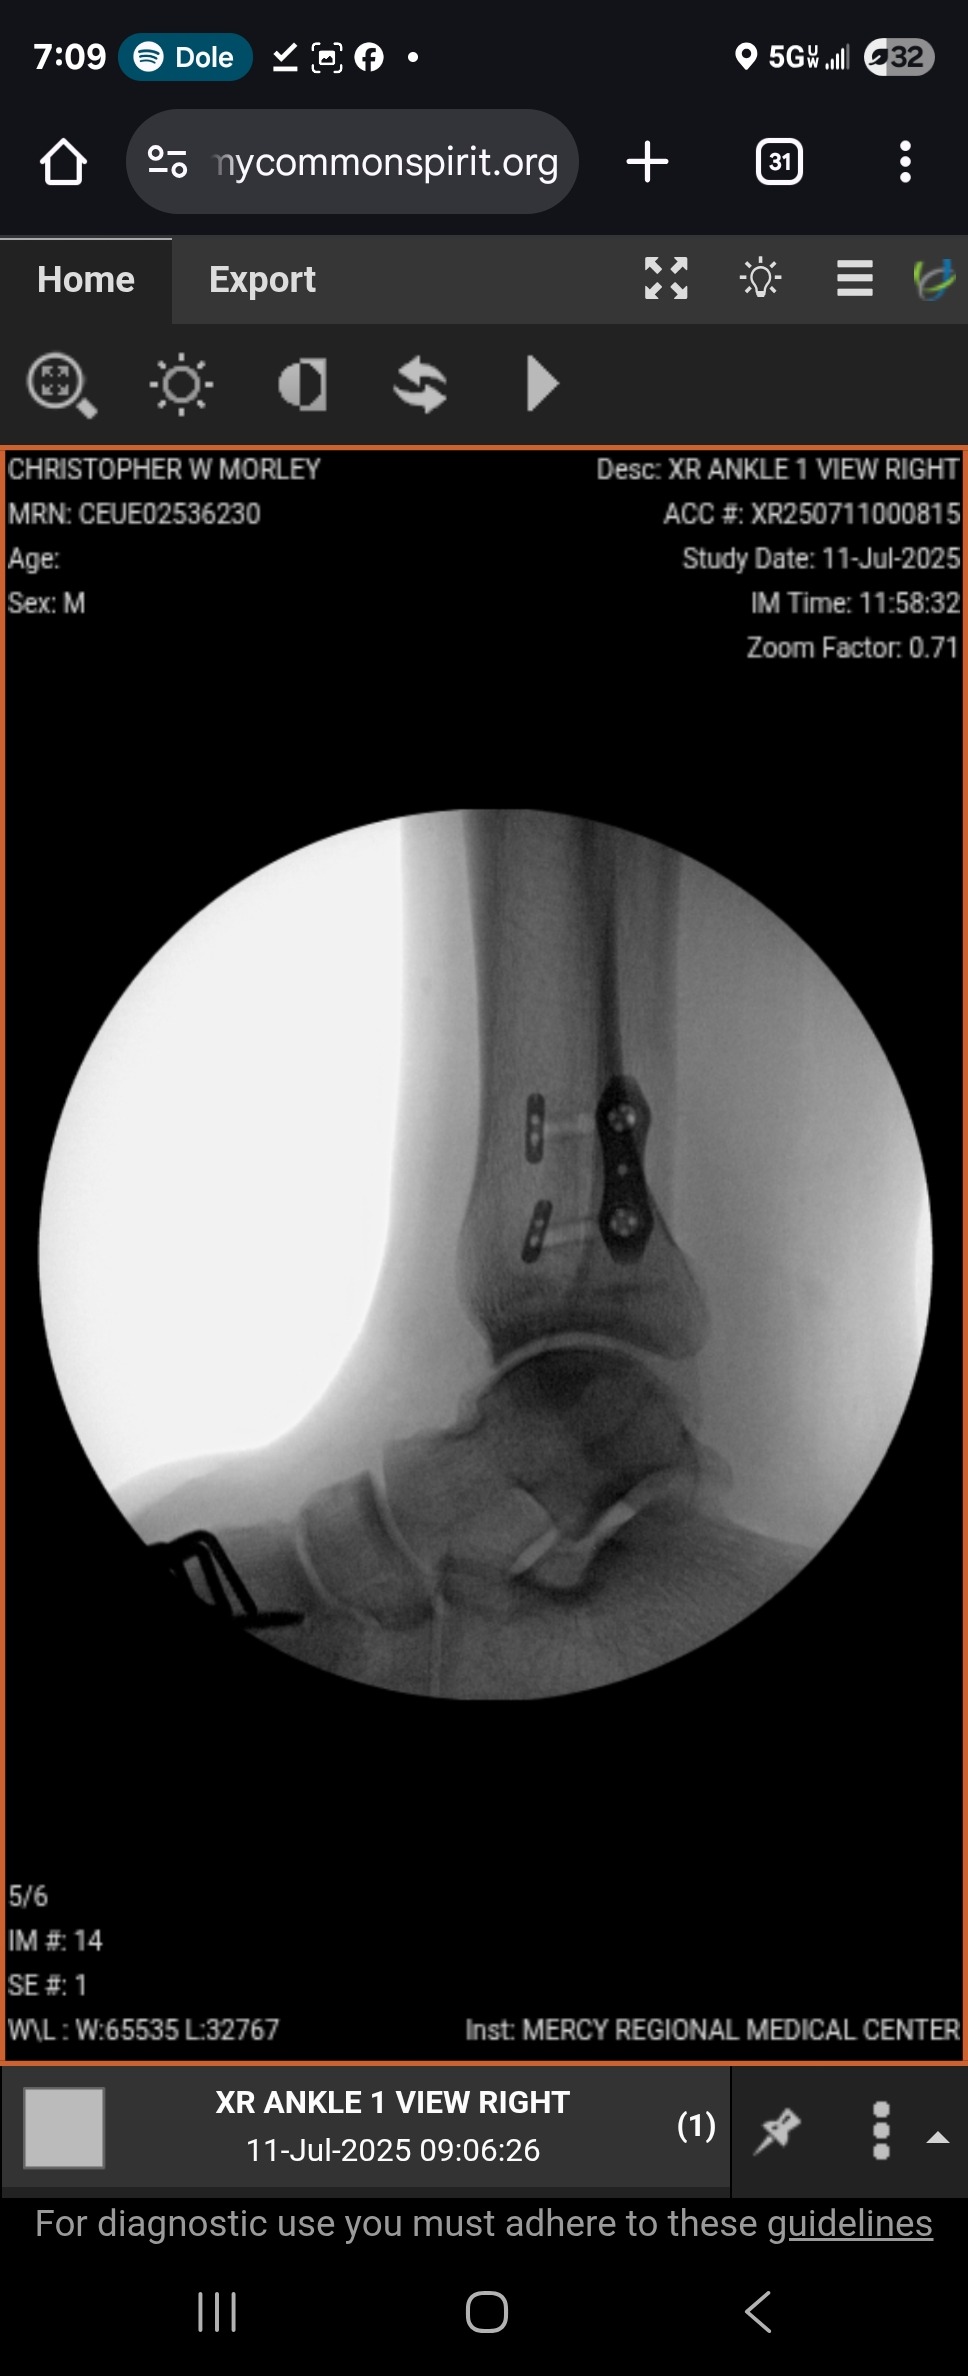

On 6/30 I was in a motorcycle accident. In the middle of a (amicable) divorce, I did something for me and it backfired; I traded some stuff for my first motorcycle. A low-speed fall on my first ride, the foot peg dug into my foot and scrambled my bones. Four out of five metatarsals were dislocated and a midfoot bone was crushed. $121K worth of surgery later, including a bone graft and several pieces of metal in my foot along with a screw, I'm in recovery.